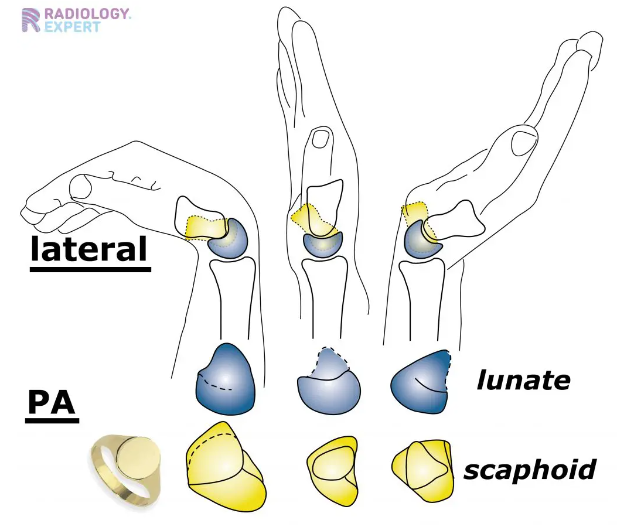

- 손목을 이루는 모든 관절에서 발생할 수 있습니다. 특히 주상골(Scaphoid)와 관련되어서 많이 발생하게 됩니다. 거의 손목의 관절염에서 90%이상이 주상골과 관련되어 있다고는 연구도 있습니다.

- 외상 후에 주상골이 잘 붙지않아 생기는 부정유합이나 무혈성 괴사가 주요 원인일 수 있고, 주상골 주변에 인접한 관절의 손상이 중요한 원인이 됩니다.

- 앞서 말했듯 퇴행은 주상골주변에서 가장 많이 발생합니다.

- 보통 처음에는 요골경상골기(Radial styloid)와 주상골의 닿는 부분에서 관절염이 우선 발생되고 이 후 주변 관절로 침범하게 됩니다.